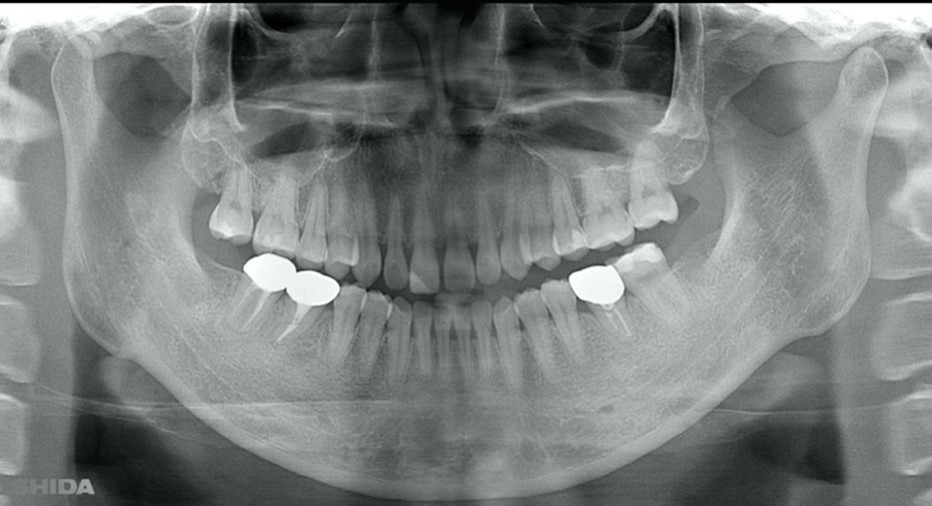

A 27-year-old female patient came to us with discomfort in the right lower jaw (Figure 1). Her primary symptoms were pain in the lower right tooth when biting and discomfort associated with not being able to chew well with the lower left single denture. The patient was married and had one young child, and previously received dental treatment in China, then had returned to Japan for childbirth and early childcare. The patient was a nonsmoker with moderate plaque control and medical history taking revealed no problems. In clinical and radiographic examinations, a root fracture was observed on tooth #46, which had been endodontic ally treated and restored with a full-cast metal crown. Periodontal probing revealed a pocket depth of 8 mm on the buccal center side of the tooth. No pain was detected with percussion and mobility of the tooth was normal. (Figure 1, Figure 2, Figure 3).

Figure 1.Clinical case of right auto transplantation. Panoramic view at initial examination.Tooth #46 was shown to be half decayed and a cystic lesion was found in the mesial root apex. Tooth #36 was lost, while #48 and #38 were present. There was a total of 29 teeth in the oral cavity.

Figure 2.Pre-treatment X-ray findings. A cystic lesion was found in the mesial and distal roots apex, and root nodule of #46.

The patient requested auto transplantation in the lower left side jaw equivalent to #36, the tooth that was missing and replaced by a removable partial denture. The basic technique and procedure were the same as previously used for treatment of #48. Prior to the operation for #36, the buccal and proximal crown widths, and root length were measured using CBCT. In such cases, it is considered important to confirm the location of the inferior alveolar nerve, as well as the amount and depth of bone cutting needed by use of preoperative CT findings so as to prepare for treatment and ensure that the donor tooth can be placed smoothly in the socket (Figure 10). A trial application went smoothly, because the tooth was formed so as to be slightly larger than the root from the donor tooth (Figure 11, Figure 12).

Figure 15.Panorama X ray image obtained one year after procedure for #36. The transplanted teeth demonstrated good function.